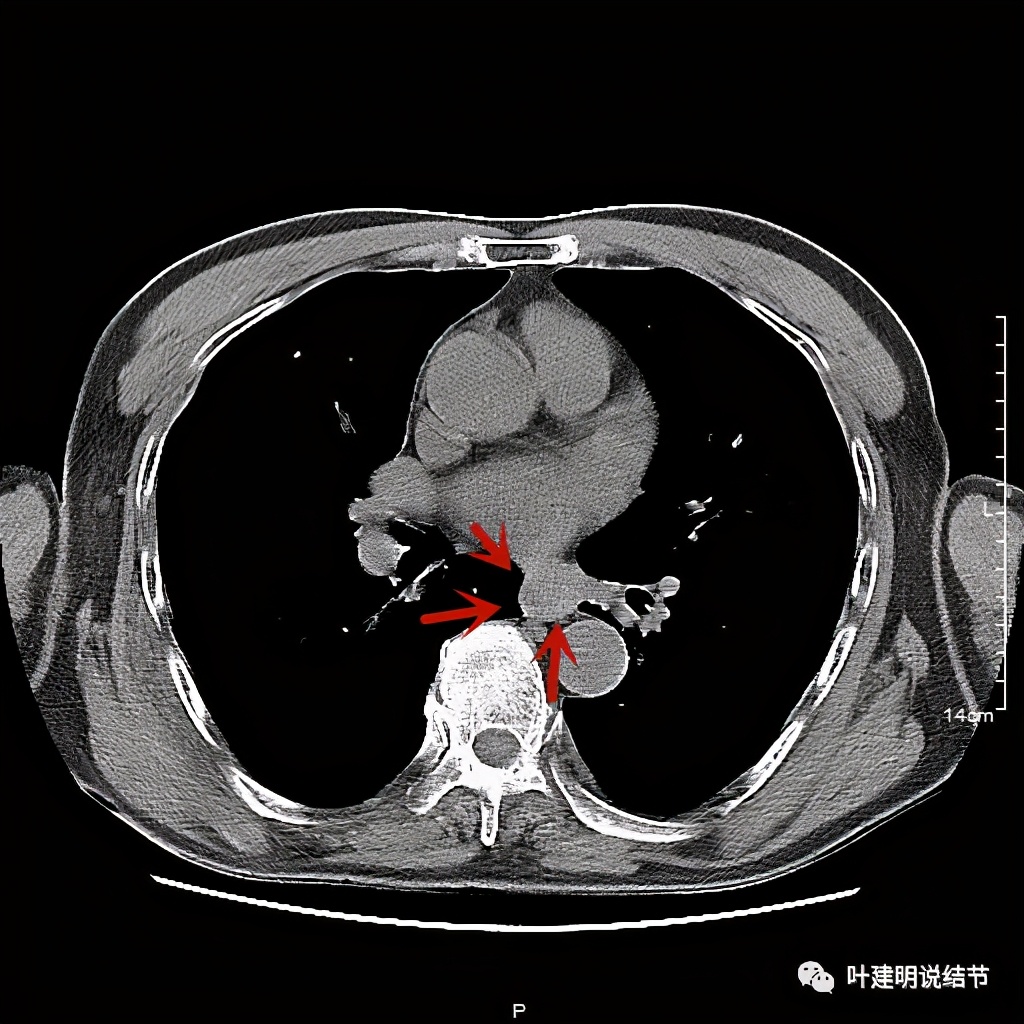

活检后食管是鳞癌,结肠是腺癌。下面是其术前CT的图像:

食管壁开始增厚

肿瘤已经较明显

位于左下肺静脉水平

红色示肿瘤

红色示肿瘤,桔色示下肺静脉,与主动脉间间隙清楚